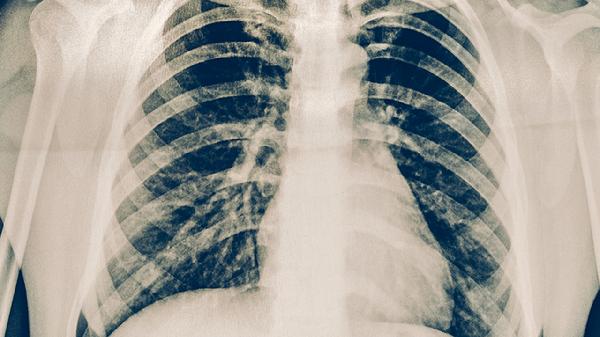

肋软骨炎一般不会转移疼痛,其特点为局部固定性疼痛。肋软骨炎是肋软骨与胸骨连接处的非特异性炎症,主要表现为前胸壁单侧或双侧局限性疼痛,可能伴随肿胀和压痛,疼痛通常不会放射至其他部位。

肋软骨炎的疼痛多呈钝痛或锐痛,在咳嗽、深呼吸、上肢活动时加重,按压病变部位可诱发明显压痛。疼痛位置固定于肋软骨交界处,常见于第2-5肋软骨,部分患者可能因炎症刺激周围神经出现牵涉痛,但并非真正的转移性疼痛。典型发作时疼痛可持续数周至数月,呈间歇性加重,但不会随病程进展改变疼痛区域。

极少数情况下,当肋软骨炎合并胸椎病变或神经根受压时,可能出现类似转移痛的放射性不适,此时需通过影像学检查排除其他疾病。若疼痛范围扩大或性质改变,需警惕带状疱疹、肋间神经痛、心源性疼痛等疾病可能。